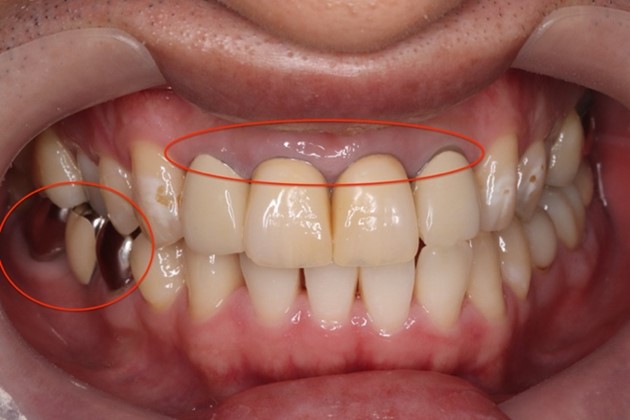

治療前の状態・主訴

目白マリア歯科|【症例】自然な美しさを考慮した審美歯科治療|治療前の口腔内写真

他院にて、数年前に前歯の治療をされましたが、次第に色が黄ばみ、最近では歯と歯茎の境目(右写真赤丸)が気になり始めたとのことです。右下(写真左下赤丸部位)の銀歯も白くしたいというご要望がありました。